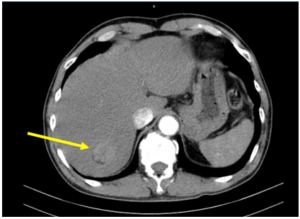

Điều trị đích bệnh nhân ung thư phổi không tế bào nhỏ có tổn thương di căn gan tại Bệnh viện Bạch Mai

Điều trị đích bệnh nhân ung thư phổi không tế bào nhỏ có tổn thương di căn gan tại Bệnh viện Bạch Mai GS. TS. Mai Trọng Khoa, PGS. TS. Phạm Cẩm Phương, PGS. Phạm Văn Thái, TS. Nguyễn Thanh Hùng, BSCKII. Thiều Thị Hằng, BSNT. Nguyễn Văn Sơn Trung...